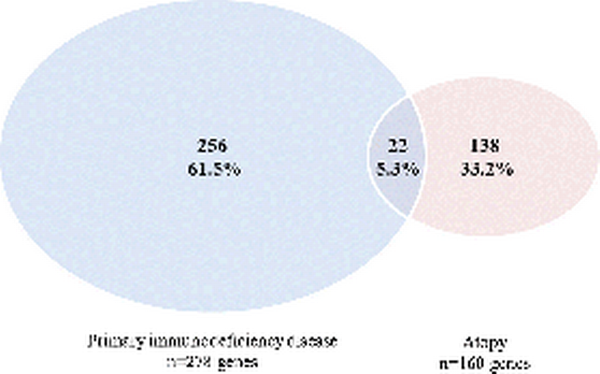

The search in HGMD on atopic manifestations retrieved 159 atopy‐related genes known in human (Additional file 1 : Table S1). Based on the overview of the IUIS, 278 disease‐causing genes of monogenic PIDs were obtained [ ]. During the cross‐check on atopy‐related mutations in PID genes, TRAF3IP2 was identified of which mutations were described that might result in an eczema phenotype. This gene did not appear in the search results of HGMD and was therefore added to the list of atopy‐related genes, resulting in a total of 160 genes for further analysis. The top three genes with the highest number of atopy‐related mutations included STAT3 (n = 107), FLG (n = 62) and DOCK8 (n = 45). Other genes had six or less atopy‐related mutations per gene (Additional file 1 : Table S1). Twenty‐two (5.3%) genes of the atopy (n = 160) and PID (n = 278) lists were overlapping, including ARPC1B, BTK, CASP8, CFTR, CTLA4, DOCK8, ICOS, IL10, IL12B, IL12RB1, IL17F, IL21, IL21R, IL7R, ITK, ORAI1, PGM3, SPINK5, STAT3, TNFRSF13B, TRAF3IP2 and TYK2 (Fig. 1 and Additional file 1 : Table S1).

Fig 1

Venn diagram illustrating the overlap of the disease causing genes of monogenic primary immunodeficiency diseases and the atopy‐related genes identified in the Human Gene Mutation Database

This is the first study that describes clusters in the clinically heterogeneous phenotype of the atopic syndrome based on gene expression profiles of immune cell lineages of healthy mice. The overlap between atopy‐related genes (n = 160) and monogenic PID genes (n = 278) was limited to 22 (5.3%) genes. We identified seven distinct clusters within the atopic syndrome based on the expression profiles of atopy‐related genes. Functional pathway analysis of all known atopy‐related genes resulted in identification of Th cell‐mediated processes underlying the atopic syndrome.

The atopic syndrome is a prevalent comorbidity in a number of PIDs, suggesting that the atopic syndrome can be a symptom of PIDs and that immune dysregulation plays a role in the pathogenesis. Interestingly, the number of overlapping genes in this study was limited (5.3%) and did not belong to one PID category according to the IUIS phenotypic classification or immunologic component [ ]. Nonetheless, the overlapping genes were bundled in just two of the seven atopy‐related gene clusters (cluster D and F), which suggests that these endotypes of the atopic syndrome are associated with the predisposition to develop a PID. However, atopy‐related mutations in these genes might differ from the disease‐causing mutations of the PIDs.